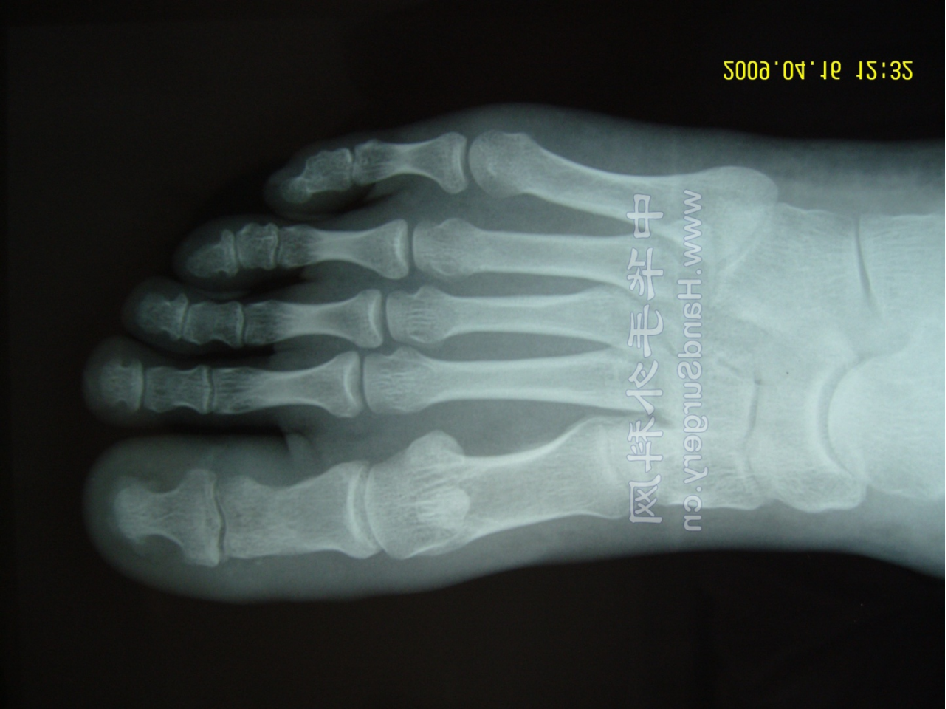

X线表现与测量

足的x线测量对于进一步了解拇外翻的病理及设计手术方案是非常重要。负重足的基本功能,很多足的畸形在负重状态下可以表现得更清楚。一些测量指标在负重和非负重状态下可以明显不同。足部各种x线测量一般都是在足负重位摄片下完成。手术前常规需要拍摄患足负重位、前后位和侧位,根据需要拍摄足的非负重位内旋斜位和籽骨轴位。

1:前后位观察和测量拇外翻角(HAA)  :拇趾跖骨中轴线与近节趾骨中轴线之夹角。正常为15°~20°

第1、2跖骨间夹角(IMA):  第1、2跖骨中轴线之夹角。正常为9 °拇外翻时此角通常大于正常。